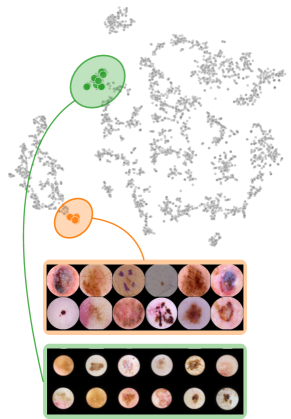

Both input and latent relevance clustering require subsequent human supervision to determine whether outlier clusters represent valid or spurious behavior. To semi-automate this process, Anders et al. [3] propose using Fisher Discriminant Analysis [37] to rank class-wise clusterings by linear separability, while Dreyer et al. [27] computes similarities between prototypes. The results of clustering approaches can serve as an initial set for bias modeling methods outlined in Sec. 3.2, which can be refined iteratively. An example outlier cluster of latent relevances is shown in Fig. 4 (top), with all samples containing the spurious band-aid concept.

Data Perspective

We first apply SpRAy in input and latent space, computing input feature importance scores using LRP summed over color channels. To obtain latent relevances, we use intermediate relevance scores in the LRP computation process after the (out of four) residual block, max-pooling over spatial dimensions to yield relevance scores for layer with channels. The clustering of pairwise cosine distances between heatmaps is shown in Fig. 6 (top left). Detected outlier clusters contain samples with spatially coherent biases, e.g., the black circle around the lesions originating from microscopes (). In contrast, clustering latent relevance scores reveals more complex, less spatially dependent clusters, as shown in Fig. 6 (top right), including the ruler artifact () and the microscope (). Compared to those in input space, the cluster for the microscope in latent space represents a more diverse high-level concept. In the input space visualization, we further highlight samples from the ruler cluster detected in latent space. Instead of forming a cluster, they spread across the entire embedding space, indicating that the bias is too complex to be detected in input space.